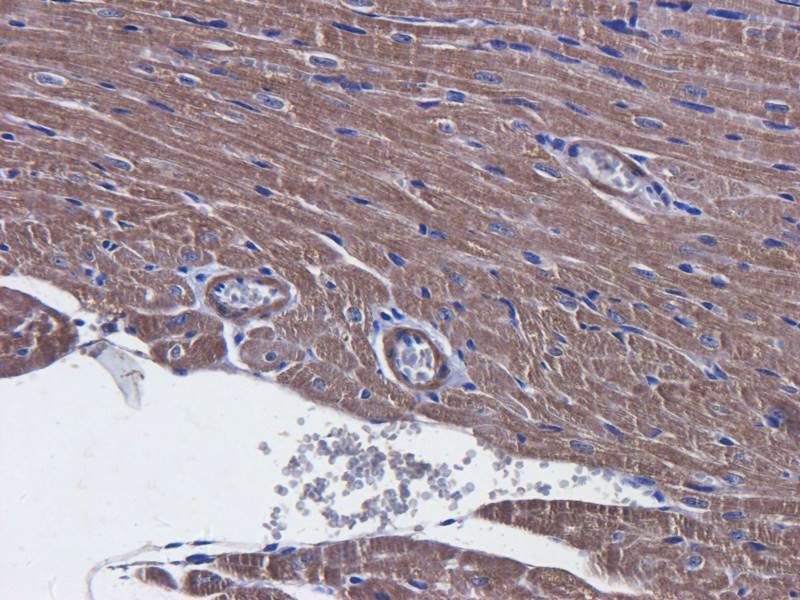

IHC staining of FFPE human brain with Ubiquitin antibody (clone PBQN-1). Required HIER: boil tissue sections in pH9 10mM Tris with 1mM EDTA for 10-20 min followed by cooling at RT for 20 min.